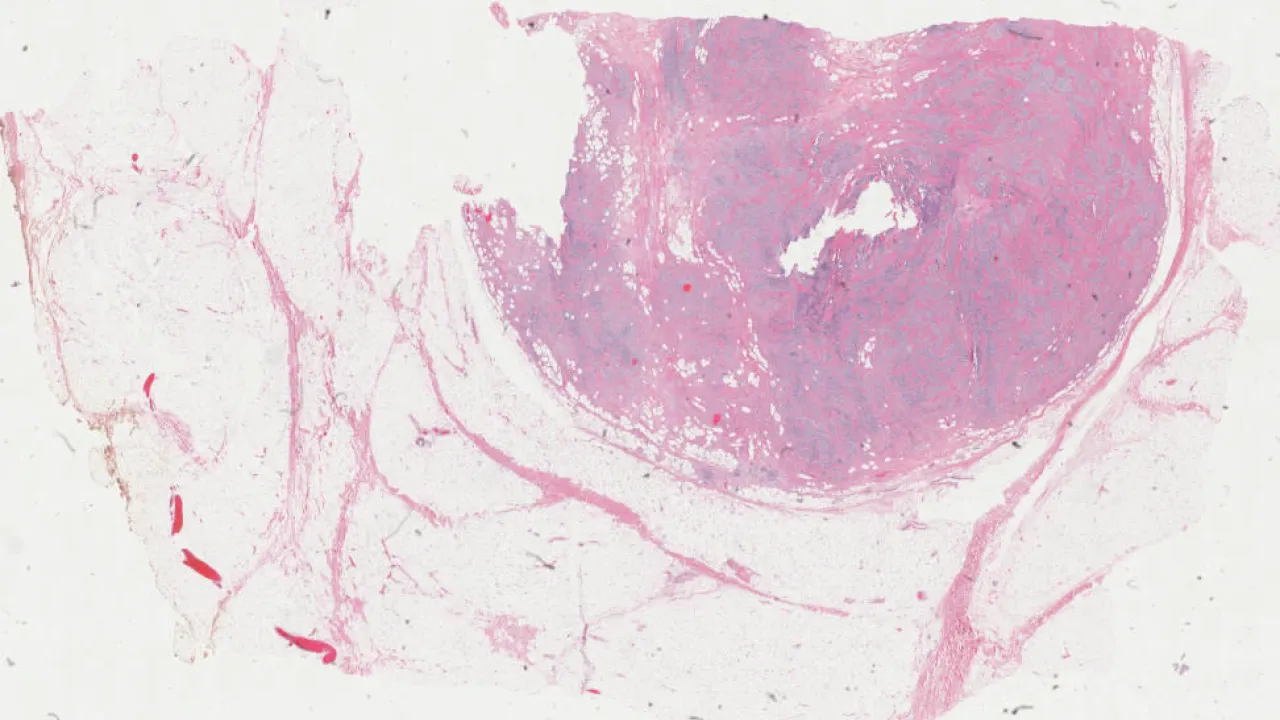

Testis, Mixed germ cell tumour, H&E stain